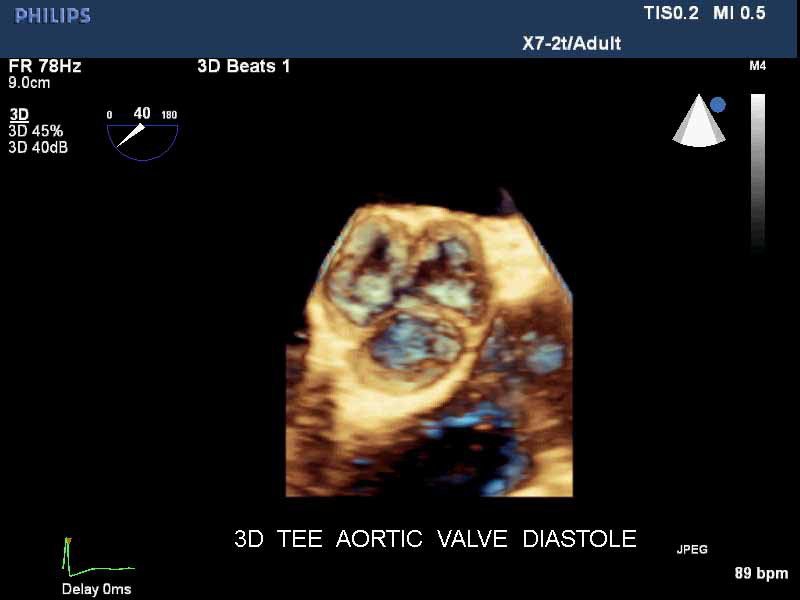

• Live 3D TEE: Эта функция позволяет проводить чреспищеводную эхокардиографию в режиме реального времени, что позволяет оценить механические сокращения сердца с точностью, необходимой для оценки результатов хирургического вмешательства.

• Чреспищеводная эхокардиография

• Чреспищеводный УЗИ датчик Philips Х7-2T